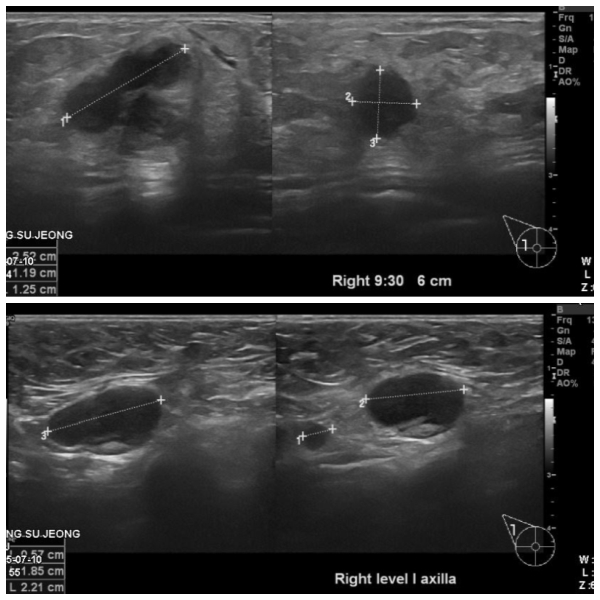

우측유방에 만져지는 혹으로 내원하신 70대 환자분이십니다.,

본원에서 우측유방 9:30 방향에 혹 조직검사와 겨드랑이에 임파선 세침검사시행하였고

결과상 침윤성유관암진단되었고 겨드랑이전이로 확인되었습니다.